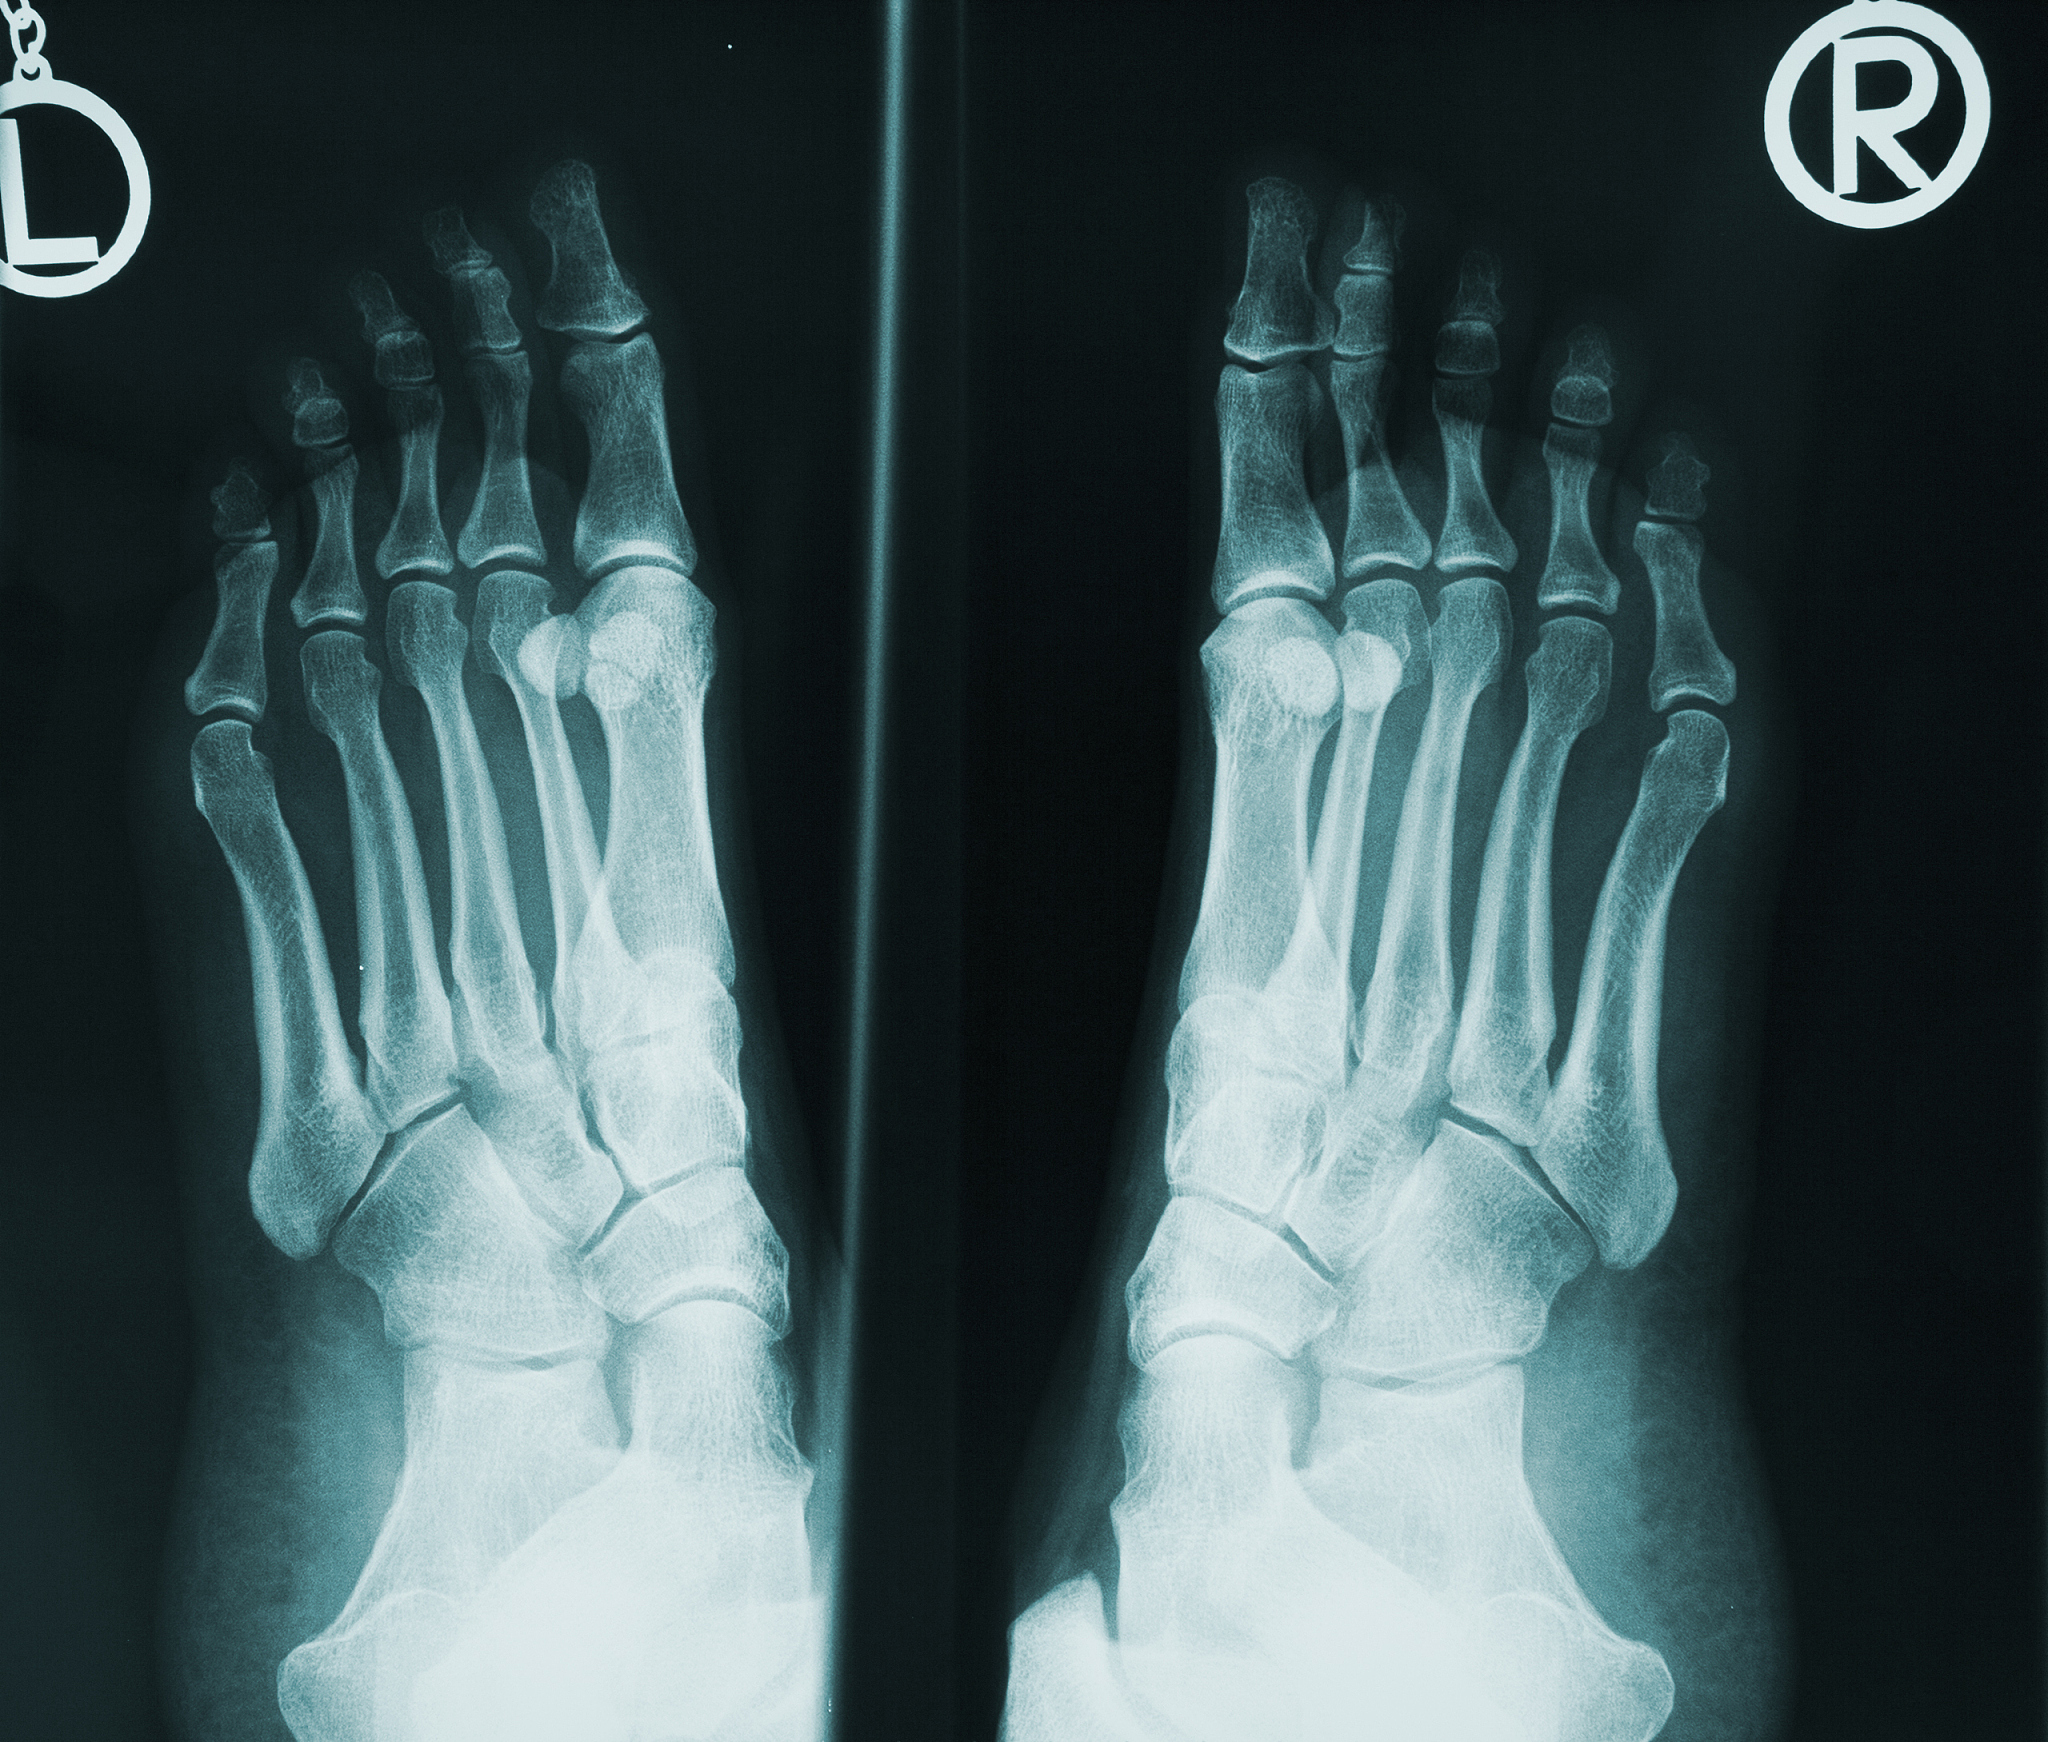

第五趾骨基底骨折,做了手术之后需要多久能脱拐走路

这取决于手术后康复的进展情况和医生的建议。通常情况下,需要在手术后进行一段时间的康复训练,包括物理治疗和康复运动。在这个过程中,患者需要遵循医生的建议,避免过度活动和受伤。通常情况下,需要1-3个月的时间才能够脱拐走路,但具体时间还需要根据个人情况而定。